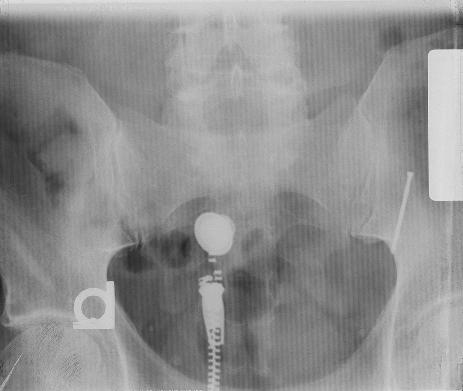

[IMAGE] X-Ray photo submitted by Tim, who says: "My father likes to play carpenter on the week-ends but is a chiropractor by trade. Last Saturday, the 19th of September, he was working on installing a new door jamb. He was keeping the casing nails that he was using for the project in his mouth. This is usually a good idea until you hit your finger with the hammer. Before he realized what happened he had swallowed one of the nails. He said it went down pretty easy. The next day he went to the office and did an x-ray to determine the nail's position."